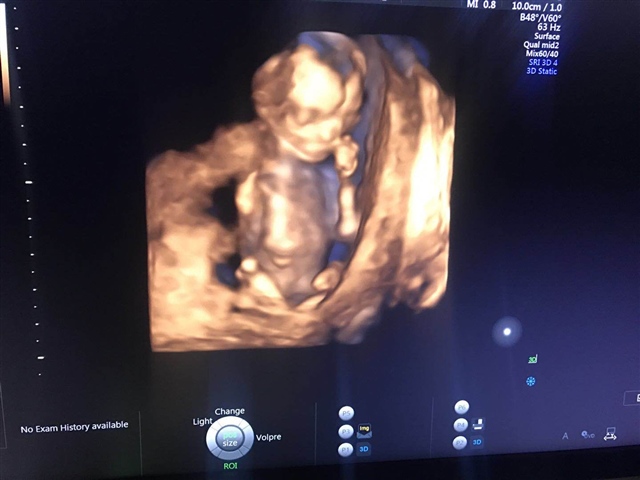

孕22周+1天

不会